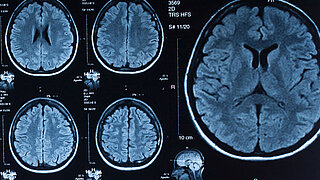

• CT Aufnahmen eines menschlichen Gehirns

Das KI-Leuchtturmprojekt KI-INSPIRE entwickelt KI-basierte Verfahren, die die Strahlendosis in der medizinischen Bildgebung reduzieren sollen.…